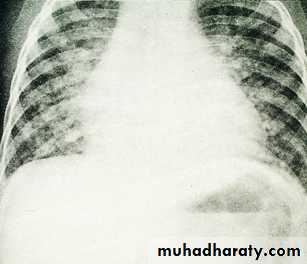

CXR OF TB

CXR in TB

1. Clinical features suggestive & high index of suspicion .2. CHEST – X- RAY : The initial suspicion of pulmonary TB based on abnormal radiographic finding in a patient with respiratory symptoms .

Any radiographic pattern-from small nodule to diffuse infiltrate may be seen . Although the ` classic `picture is that of the upper lobe with infiltrate & cavities .

CXR OF TBDiagnosis of TB